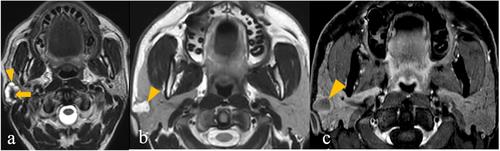

Two head and neck radiologists retrospectively evaluated and developed signatures of common benign and malignant parotid tumours using morphology and signal intensity–related variables for 98 patients on MRI available in PACS from 01 January 2016 to 26 December 2022. T1 weighted image (WI), T2WI, short tau inversion recovery, diffusion WI/apparent diffusion coefficient and postcontrast T1WI sequences were evaluated. The developed MRI signatures were then validated by a blinded third radiologist.

Sensitivity, specificity, accuracy, positive and negative predictive values using MRI signatures were 92.31%, 100%, 94.23%, 100% and 81.25%, respectively, for benign and malignant nature of parotid tumours with a highly significant p-value (< 1e-04). Developed MRI signatures also showed high statistical performance and significant p-value for parotid tumour histopathologies and grades of mucoepidermoid carcinoma (MEC). T2 signal intensity and enhancement patterns can help identify low-grade MEC, impacting management decisions regarding elective neck dissection.